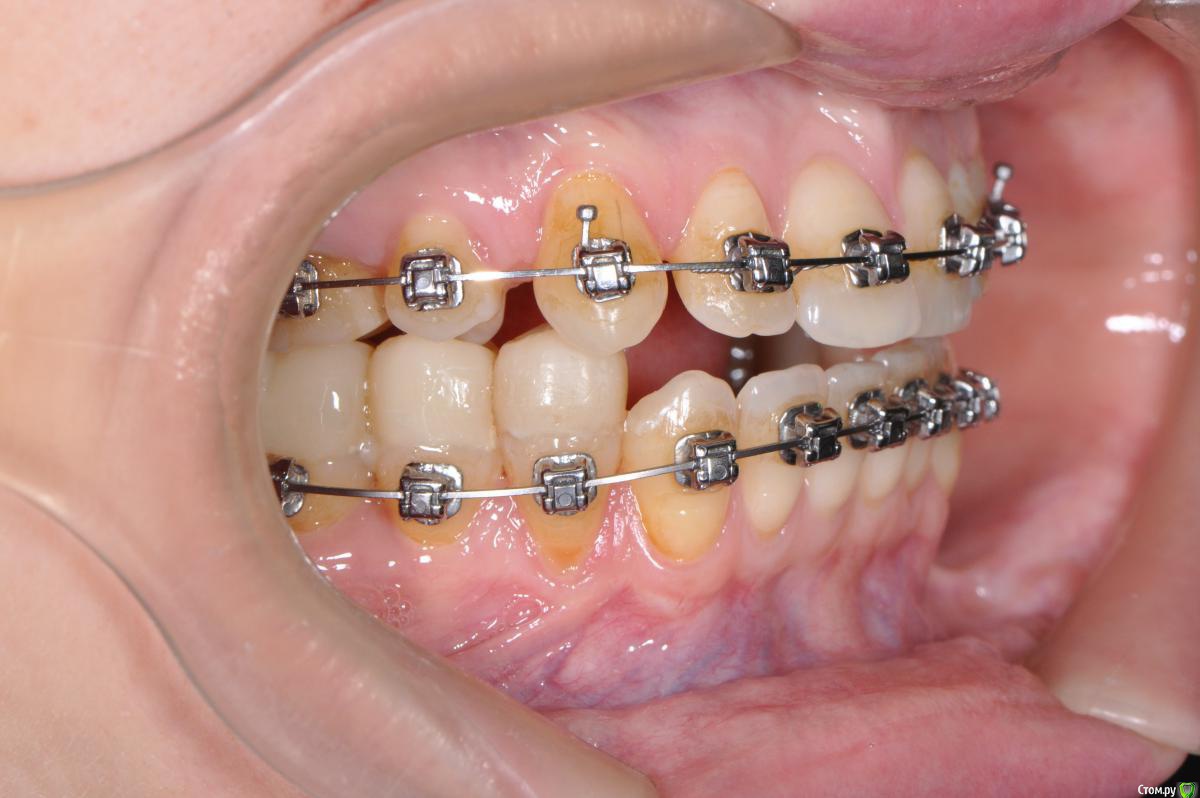

losenok83 Опубликовано 4 сентября, 2016 Автор Поделиться Опубликовано 4 сентября, 2016 Здравствуйте, очень нужна ваша помощь снова! Я обошла много ортодонтов в своем городе на предмет дальнейшего лечения. В конце концов мое самочувствие более менее менее улучшилось только после ортотика. В дальнейшем мне сказали ортодонт поставит мои зубы на такую высоту. Скажите пожалуйста это правда возможно, на такую высоту вытянуть свои верхние и нижние зубы? И еще изначально этот ортодонт планировала что в этом ортотике Н,Ч, выйдет вперед , а потом ее расширят. Поскольку этого не произошло, сказала что просто раздвинут место для раннее удаленных 4-рок на В,Ч. пружинами. А я очень боюсь, что в результате зубы будут торчать вперед как раньше.Разве нет? Расчет ТРГ на данный момент лечения. И вид челюстей в ортотике. Ссылка на комментарий

losenok83 Опубликовано 8 сентября, 2016 Автор Поделиться Опубликовано 8 сентября, 2016 Алексей Олегович, И вместе с зубами корни не вылезут? Там же высота ортотика миллиметров 5 если не больше! А что вы скажете по поводу раздвижения на В.Ч места для 4-рок пружинами. Ведь у меня до лечения был дистальный прикус при отсутствии уже одной 4-ки! Т.е. раздвинув просто зубной ряд, реально добиться правильного смыкания? Ссылка на комментарий